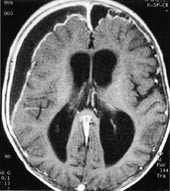

Iskemiske hjerneforandringer avdekkes hos et stort antall pasienter i de høyere aldersgrupper, ofte uten at de relativt iøynefallende MR-funn gir symptomer. Demyelinisering er også ganske lett å fremstille ved en rekke MR-sekvenser, og MR har etter hvert utviklet seg til å bli uunnværlig i diagnostikken av multippel sklerose (15, 16) (fig 5).